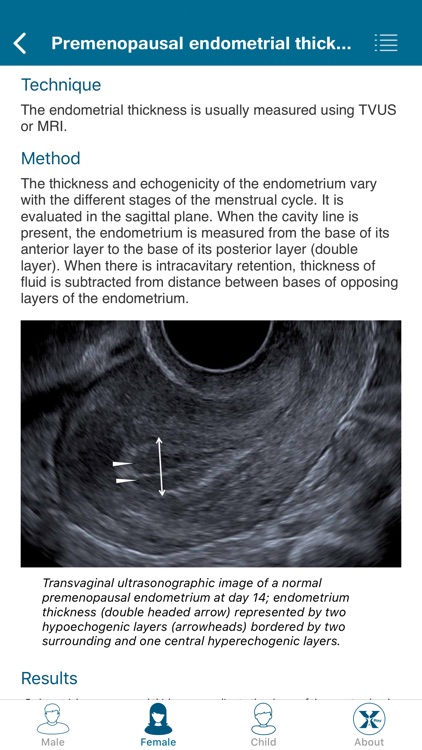

Created by radiologists for all those who practice medical imaging, this application constitutes an atlas of the main measurements in radiology and their normal values based on the most cited literature. It illustrates easy and reproducible methods using different imaging methods.

Created by radiologists for all those who practice medical imaging, this application constitutes an atlas of the main measurements in radiology and their normal values based on the most cited literature. It illustrates easy and reproducible methods using different imaging methods.

The application covers multiple imaging modalities: radiography, ultrasound, CT and MRI. The modules are divided into six sub-specialties: osteoarticular, cervical region, thorax, cardiovascular, abdomen and pelvis.